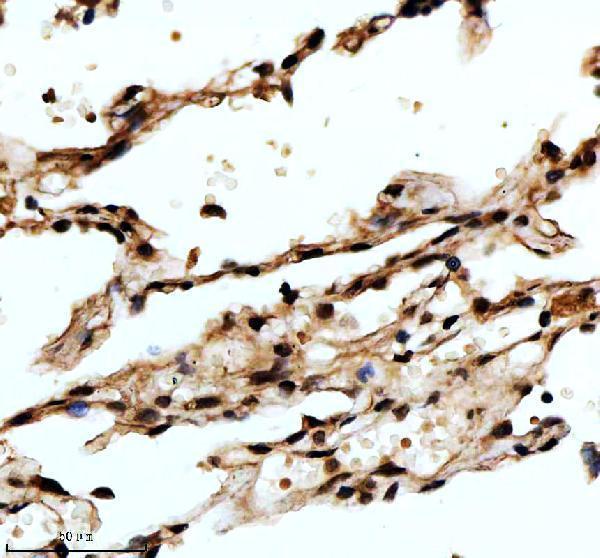

Expressed in lung and placenta.